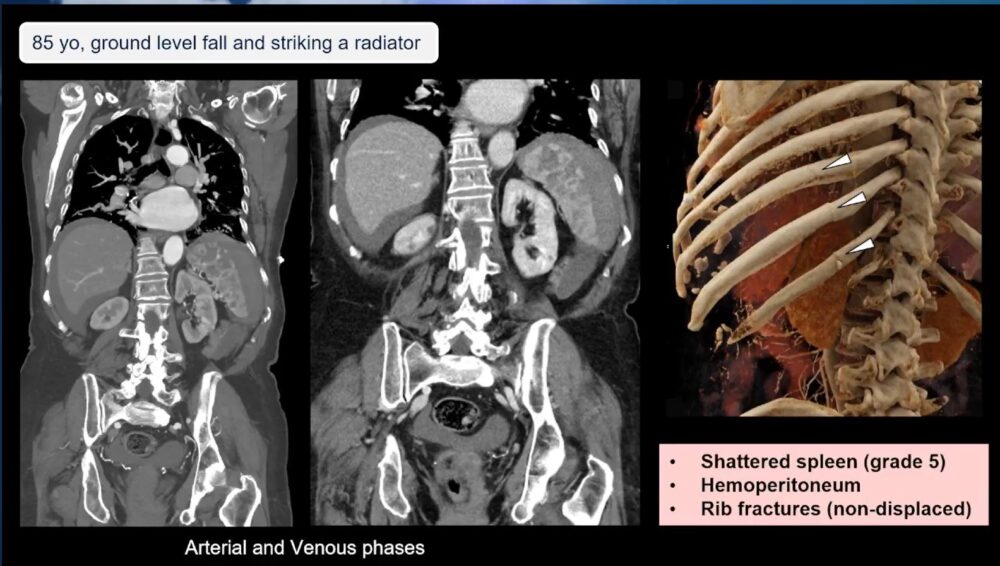

The benefits of using CT scans are not just limited to detecting fractures. In cases where internal bleeding is suspected, contrast-enhanced CT with multiphase imaging (arterial and venous phases) is crucial to fully assess the situation. Dr. Blanco Barrio addressed concerns about the use of contrast in elderly patients, particularly those with pre-existing renal conditions. While it’s true that the elderly are more likely to have chronic kidney disease, she clarified that IV contrast should not be withheld unless absolutely necessary.

“Even if the filtration rate is less than 30, give IV contrast. Follow the regular protocol,” she advised, noting that the risk of undetected injuries often outweighs concerns about contrast-induced nephropathy.